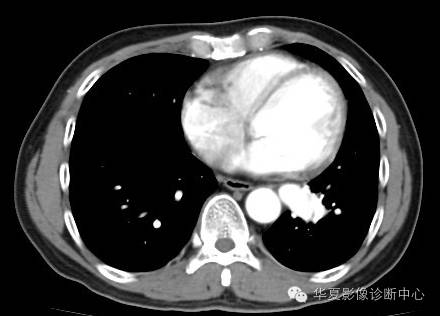

| 影像表现及分析: | 影像表现:定位左下叶;左下叶体积缩小,整体密度增高,支气管分布正常,其内见血管增多,但是走形正常,未见杂乱、迂曲的血管影;血管连向肺门下方软组织密度结节灶,结节与主动脉分界不清,增强后,见降主动脉发出异常粗大血管供血整个左下叶,左下肺动脉细小。 |

异常体动脉供应正常下肺基底段完整含义为起源于降主动脉的异常动脉供应下肺基底段,而基底段支气管树和肺实质正常,同时基底段肺动脉缺如或狭窄【大部分缺如(完全型),部分狭窄(不完全型)】;95%以上累及左下肺,因此也称为异常体动脉供应正常左下肺基底段。 病因尚未明确,可能是胚胎发育时期供应肺芽的背主动脉原始小分支退化不全,与肺实质形成异常连接,并影响肺动脉与肺血管床连接而导致此部位肺动脉发育不良,而支气管、肺组织的发育未受影响。本病的病理生理基础为左向左的分流,体动脉供应的肺组织充血,体循环的高压可增加肺血管床的压力和左心负荷,同时也增加肺循环量和压力而增加右心负荷,导致各种临床症群。本病可无临床症状,部分患者可有咯血、呼吸道感染、呼吸困难、充血性心力衰竭。 影像表现:左肺下叶体积缩小,整体密度稍增高,支气管树走形、分布正常,血管增多、稍增粗;增强后显示左下肺动脉幼小,甚至不发育;下叶由主动脉发出的粗大血管供血。 |